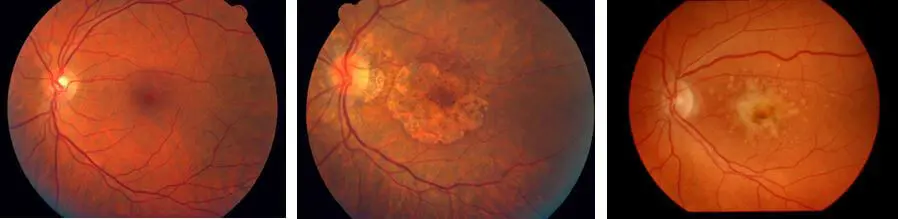

Izquierda: Retina Normal | Centro: DMAE Atrófica | Derecha: DMAE Húmeda

La DMAE (degeneración macular asociada a la edad) es una enfermedad degenerativa de la mácula (zona que utilizamos para la visión central) Representa la primera causa de baja visión irreversible en mayores de 65 años. Siendo la edad el principal factor de riesgo; actualmente se demostró una gran asociación genética (de importancia conocer si sus familiares la padecieron). Además de la carga genética, los factores como el tabaquismo, hipertensión, obesidad y otros, constituyen factores ambientales que predisponen a la DMAE.

Se daña progresivamente los fotorreceptores y el epitelio pigmentario de la mácula responsables de la visión de los colores y de agudeza visual. La DMAE le hace perder la visión central. No puede ver los detalles finos, ni de cerca ni de lejos.

Comúnmente se la clasifica en dos tipos que pueden alternarse según la evolución de la enfermedad:

• Degeneración macular seca o NO EXUDATIVA: Es la forma más frecuente de presentación (más del 80% de los casos) y evoluciona de forma lenta. No existen tratamientos actuales que puedan revertir su evolución.

• Degeneración macular EXUDATIVA (húmeda): Es menos frecuente, pero de evolución rápida y de pronóstico reservado. Se caracteriza por la formación de neovasos debajo de la retina. Este crecimiento produce una incapacidad de los vasos para contener líquido y por ello se la llama húmeda (produciendo edema macular).